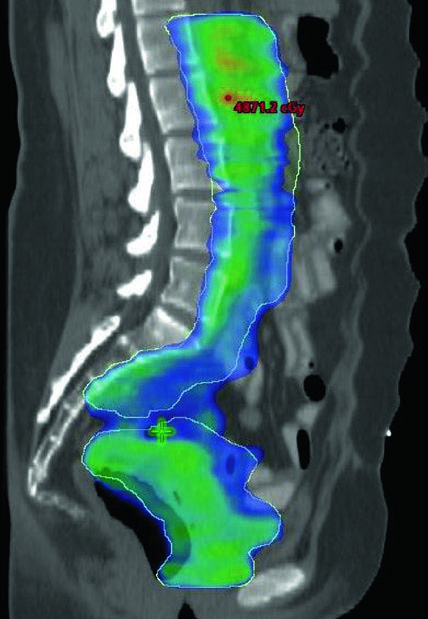

A boost of 5-15 Gy may be added for gross nodal disease or parametrial involvement, delivered either sequentially or as a simultaneous integrated boost (SIB). The textbook illustrates a patient with FIGO stage IB endometrioid adenocarcinoma, post robotic-assisted laparoscopic hysterectomy, who had an enlarged para-aortic lymph node found at CT simulation. She was treated with extended field IMRT using an ITV technique. The superior border of CTV3 was modified to include the renal hilum, the GTV of gross nodal disease was contoured, and it received a planned SIB boost of 5940 cGy with 4760 cGy in 28 fractions to the remaining nodes.

The SIB approach allows treating gross nodal volumes with escalated dose without adding extra fractions. In clinical practice, the choice between SIB and sequential boost depends on case geometry and dose constraints to adjacent organs at risk. For complementary approaches in definitive gynecologic IMRT, see the dedicated article.